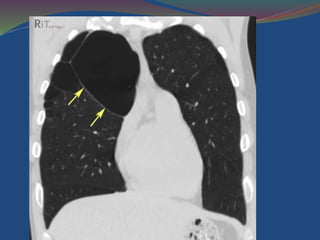

High-resolution computed tomography images through the lung apices and

bases demonstrate lower lobe predominate emphysema

Lower-lung predominance, and vascular attenuation are better shown by the coronal

minimum intensity projection and maximum intensity projection images .

High-resolution computed tomographyimages through the lung apices and bases demonstrate lower lobe predominate emphysema

• 64.

Lower-lung predominance, andvascular attenuation are better shown by the coronal minimum intensity projection and maximum intensity projection images .